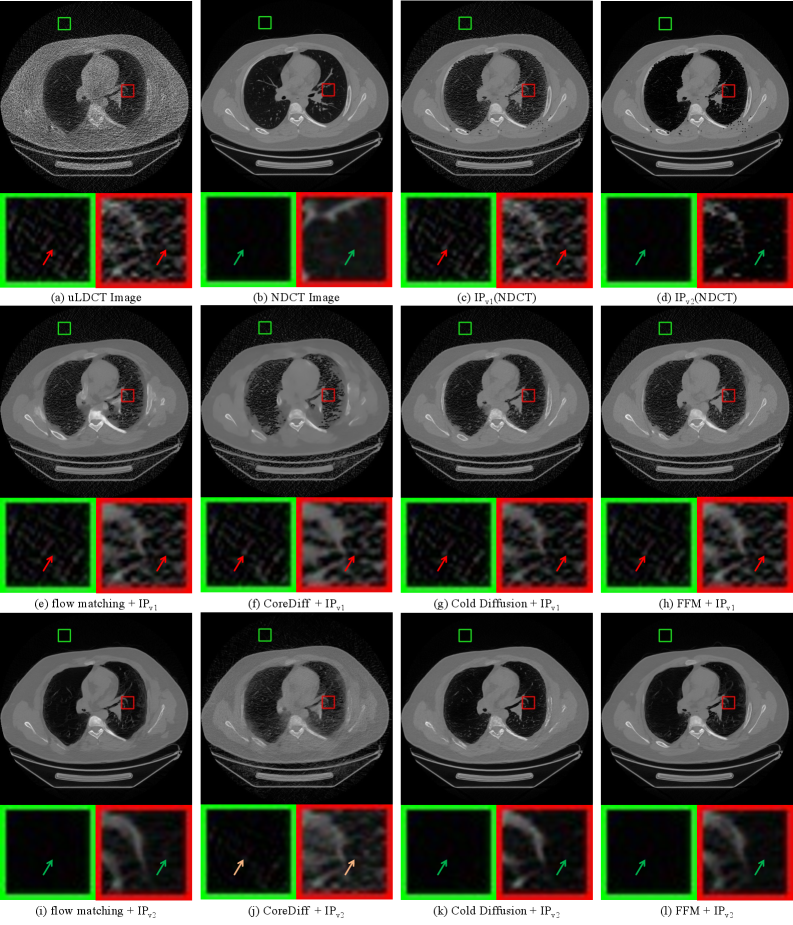

4.3.3 Visual Quality

Figure 3 presents a visual quality comparison of different methods on test set samples. Close-up views of the magnified regions clearly show that models trained with the IPv1 strategy fail to achieve effective denoising in both the background and lung parenchyma areas, with noise levels in these regions nearly identical to those in the input ultra-low-dose images. In contrast, models trained with the IPv2 strategy exhibit notable noise suppression in the background, while the textural structures within the lung parenchyma are also markedly restored. This visual comparison aligns closely with the quantitative results discussed above, providing intuitive and compelling evidence for the effectiveness of the IPv2 strategy.

Refer to caption

Figure 3: Comparison of visual quality for various denoising methods under the previous purification strategy (IPv1) and the proposed strategy (IPv2). (c) Label constructed with IPv1, (d) Label constructed with IPv2. Red arrows indicate the presence of noise, green arrows indicate the absence of noise, and yellow arrows indicate slightly inferior denoising performance.